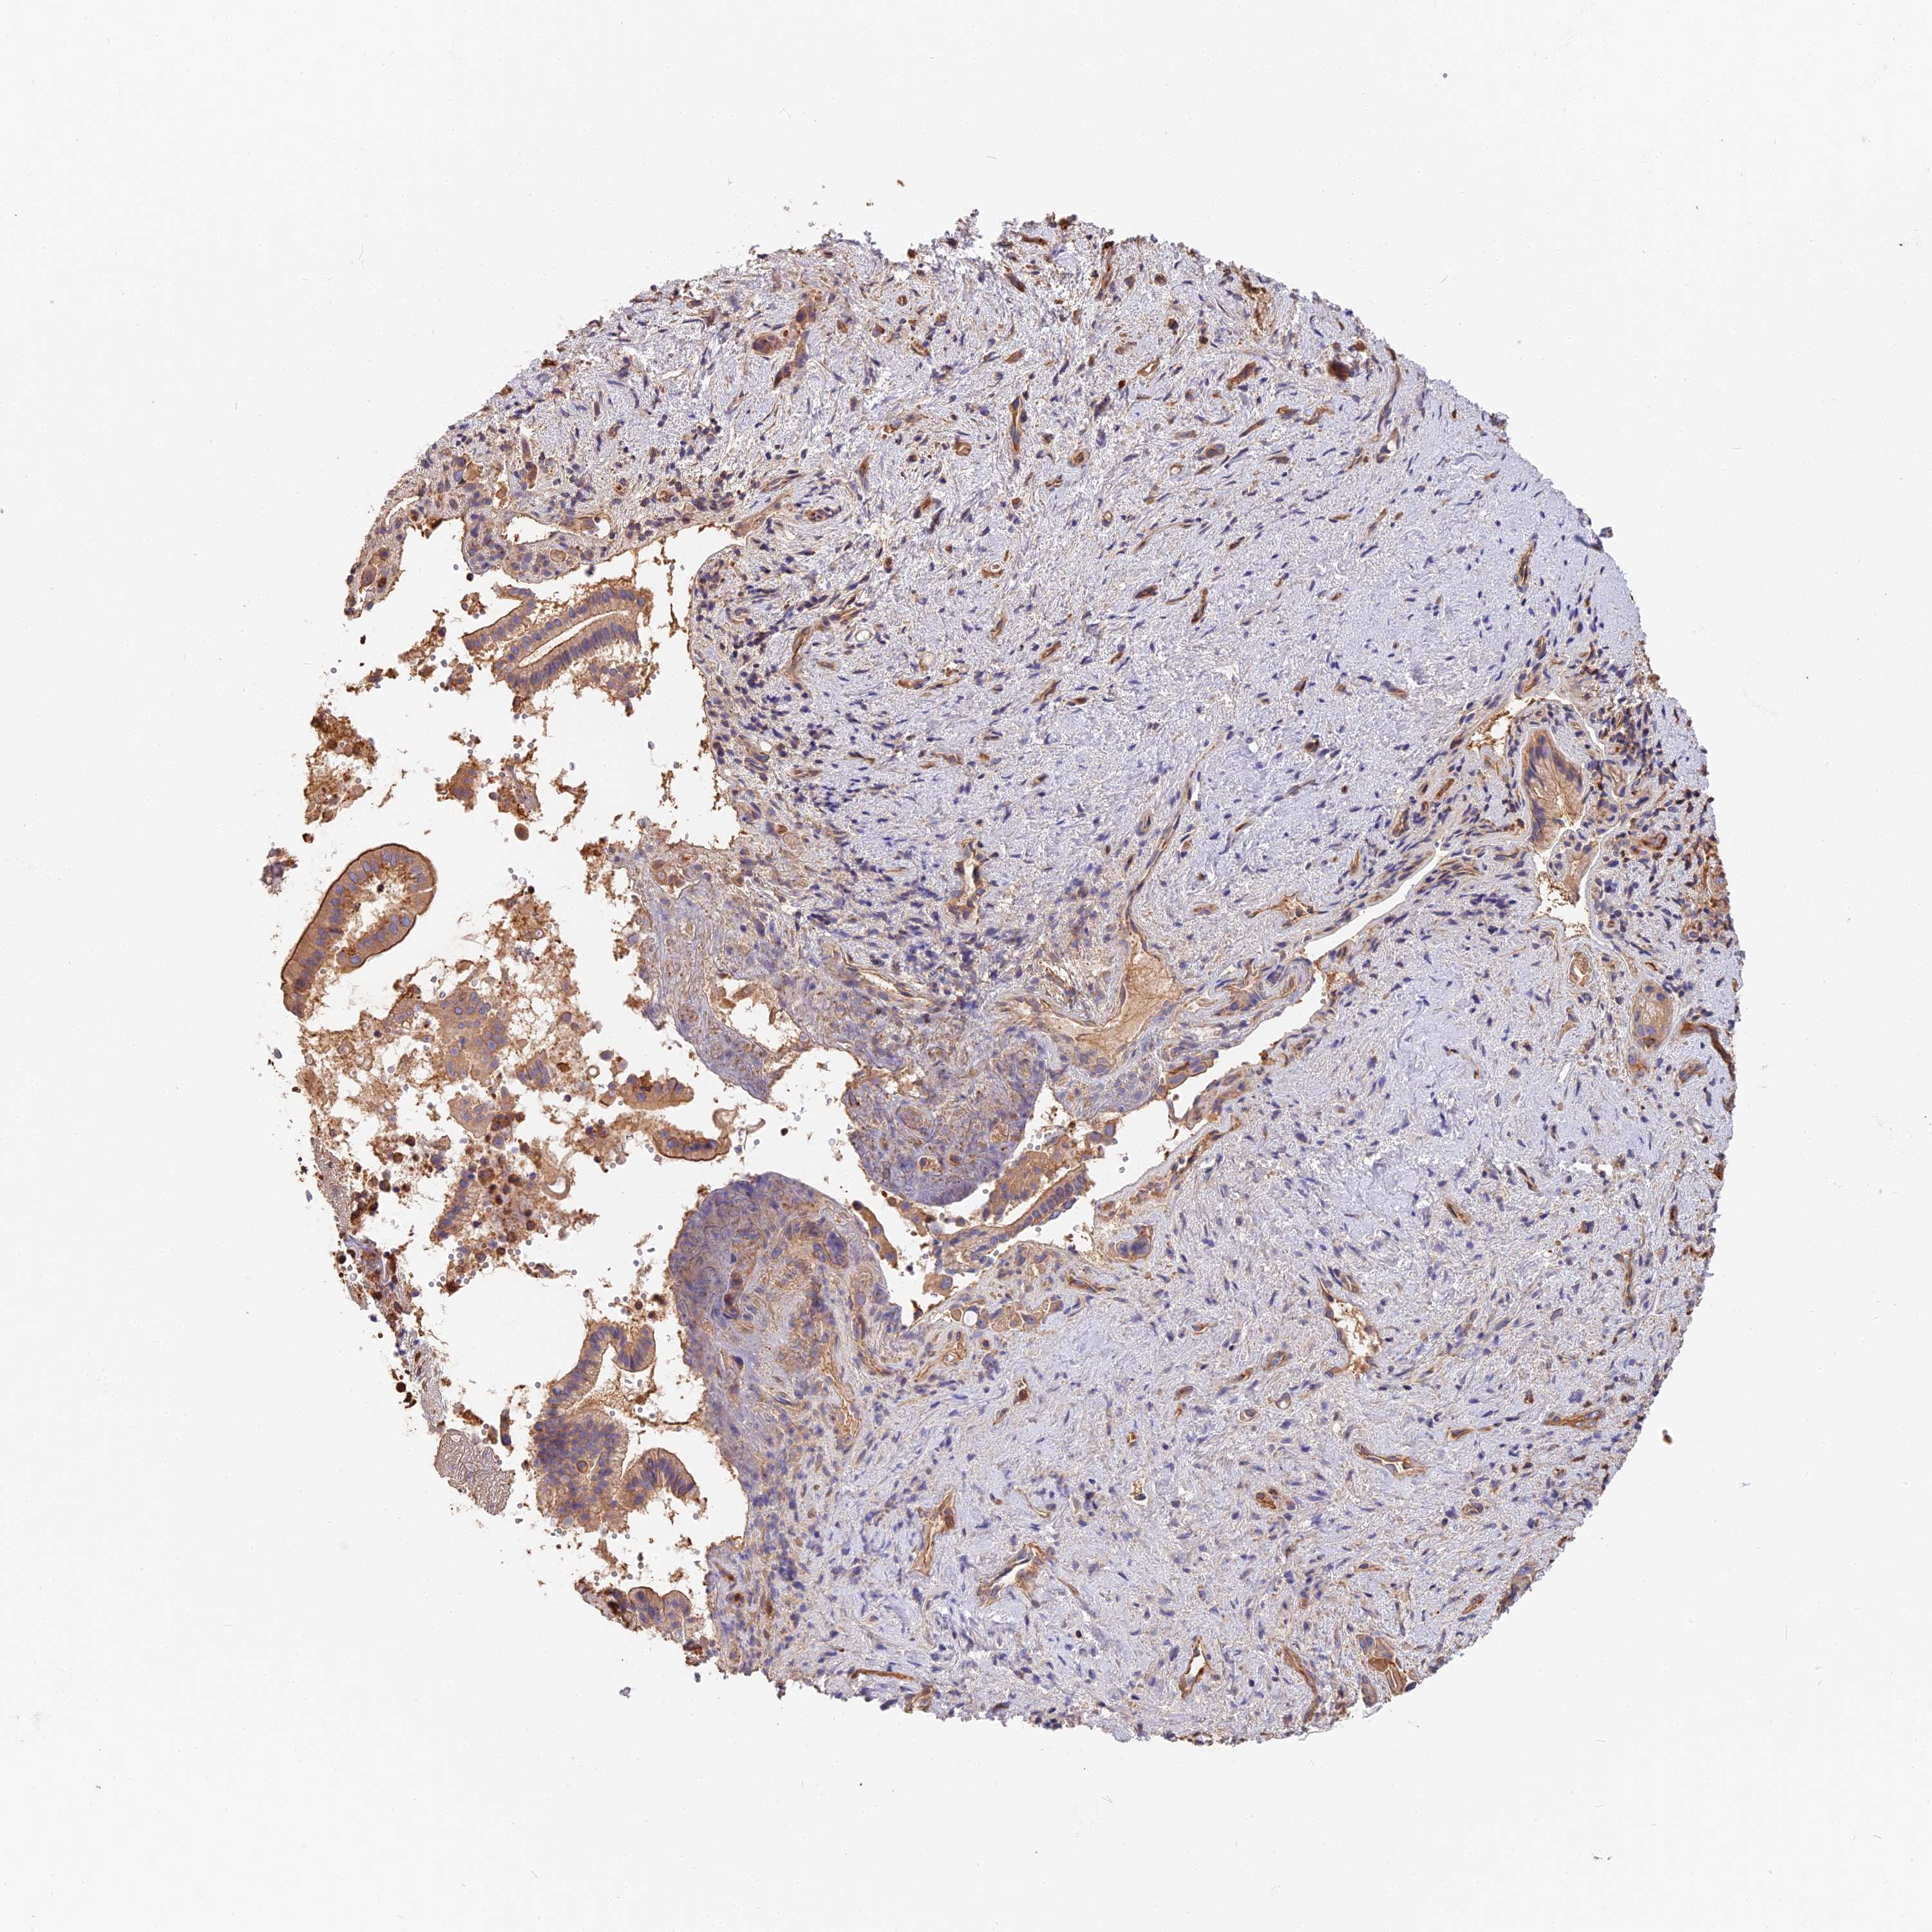

PANCREATIC CANCER - Protein expressioni

A mouse-over function shows sample information and annotation data. Click on an image to view it in a full screen mode. Samples can be filtered based on level of antibody staining by selecting one or several of the following categories: high, medium, low and not detected. The assay and annotation is described here.

Note that samples used for immunohistochemistry by the Human Protein Atlas do not correspond to samples in the TCGA dataset.

Antibody stainingi

Antibody staining in the annotated cell types in the current human tissue is reported as not detected, low, medium, or high, based on conventional immunohistochemistry profiling in selected tissues. This score is based on the combination of the staining intensity and fraction of stained cells.

Each image is clickable and will lead to virtual microscopy that enables deeper exploration of all samples and also displays staining intensity scores, fraction scores and subcellular localization as well as patient and tissue information for each sample.

Antibody HPA040701

Staining

High

Medium

Low

Not detected

Intensity

Strong

Moderate

Weak

Negative

Quantity

>75%

75%-25%

<25%

None

Location

Nuclear

Cytoplasmic/membranous

Cytoplasmic/membranous,nuclear

Adenocarcinoma, NOS